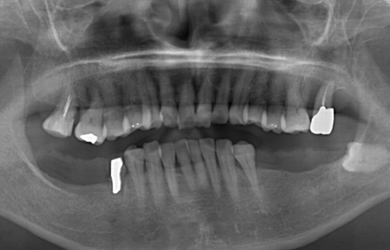

インプラントの症例写真 IMPLANT

スピードインプラント治療+セラミック治療

| 主訴 | 歯の無い部分にインプラント治療を受けたい。 | ||||||||||||||||||||||||||||||||

| 治療方針 | 抜歯と同時にインプラント治療を行うことにより、治療期間を短縮。 | ||||||||||||||||||||||||||||||||

| 治療内容 | インプラント4本(通常インプラント3本、抜歯即日スピードインプラント1本)、ハイブリッドセラミック5本 | ||||||||||||||||||||||||||||||||

| 総治療費 | 1,385,800円 | ||||||||||||||||||||||||||||||||

| 治療期間 | 4ヵ月+6ヶ月 |